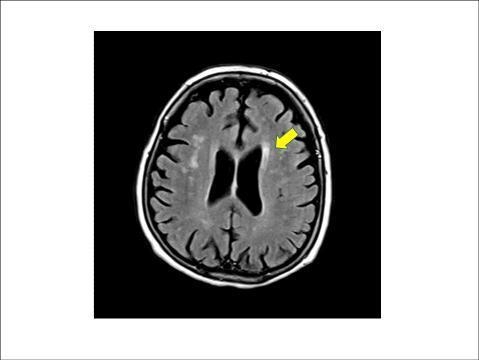

연구팀은 분석 대상자의 거주지역별 연평균 미세먼지 농도를 연간 노출량으로 추정하고 1년간의 노출량 차이가 '뇌 백질 변성(WMH)', '무증상(열공성) 뇌경색', '뇌 미세출혈' 등의 병변과 어떤 연관성이 있는지를 분석했다. 조사 기간 중 전체 지역의 미세먼지 평균 농도는 49.1㎍/㎥이었다.

뇌 백질은 MRI 영상에서 뇌 중심부 옆으로 하얗게 보이는 부분을 말하는데, 이 백질에 퍼져 있는 작은 혈관들이 손상된 상태를 뇌 백질 변성이라고 한다. 또 무증상 뇌경색은 뇌 속 작은 혈관이 막혀 생기는 질환을 일컫는다.

이들 질환 모두 MRI에서 무증상의 병변으로 보이지만, 점차 뇌 노화가 비정상적으로 진행되면서 뇌졸중이나 치매 등 심각한 질환으로 이어질 수 있다.

연구팀은 미세먼지 농도가 10㎍/㎥ 증가할 때마다 뇌 백질 변성 면적이 약 8%씩 증가하는 것으로 추산했다. 또 같은 조건에서 무증상 뇌경색이 발생할 위험은 약 20% 더 높아지는 것으로 평가했다.